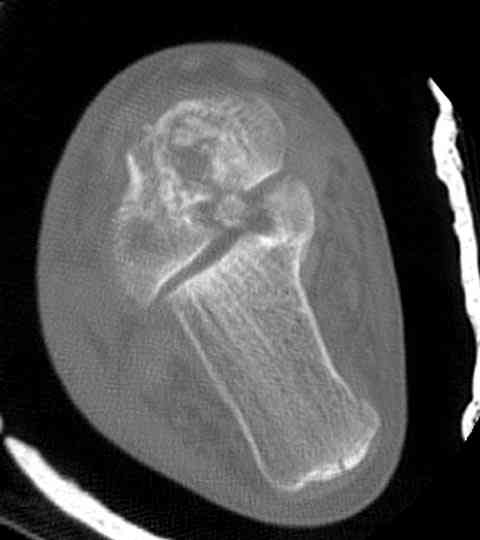

Для оценки состояния нужны дополнительные исследования, например Canale или Broden ренгенограммы и Компьютерная томография.

Случай с множественным оскольчатым переломом тарана оперированный из двойного доступа.